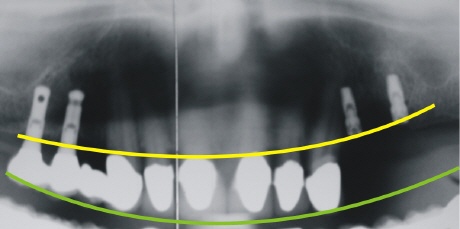

Links auf dem Röntgenbild sieht man zwei bereits versorgte Implantate. Rechts wurden zwei neue Implantate eingebracht. Man beachte rechts eine bis zur Kauebene (grüne Linie) zu überbrückende erhebliche Strecke durch den späteren Zahnersatz.

Statische Fehlversorgung

Die Pfeile verdeutlichen das statische Problem rechts auf dem Bild. Es besteht ein erhebliches Missverhältnis zwischen dem Kraftarm, symbolisiert durch den gelben Pfeil (entspricht der Implantatlänge), und dem Hebelarm, symbolisiert durch den roten Pfeil (entspricht der Kronenlänge).

Links im Röntgenbild zeigt sich dagegen ein günstiges Verhältnis von Kraftarm und Hebelarm.